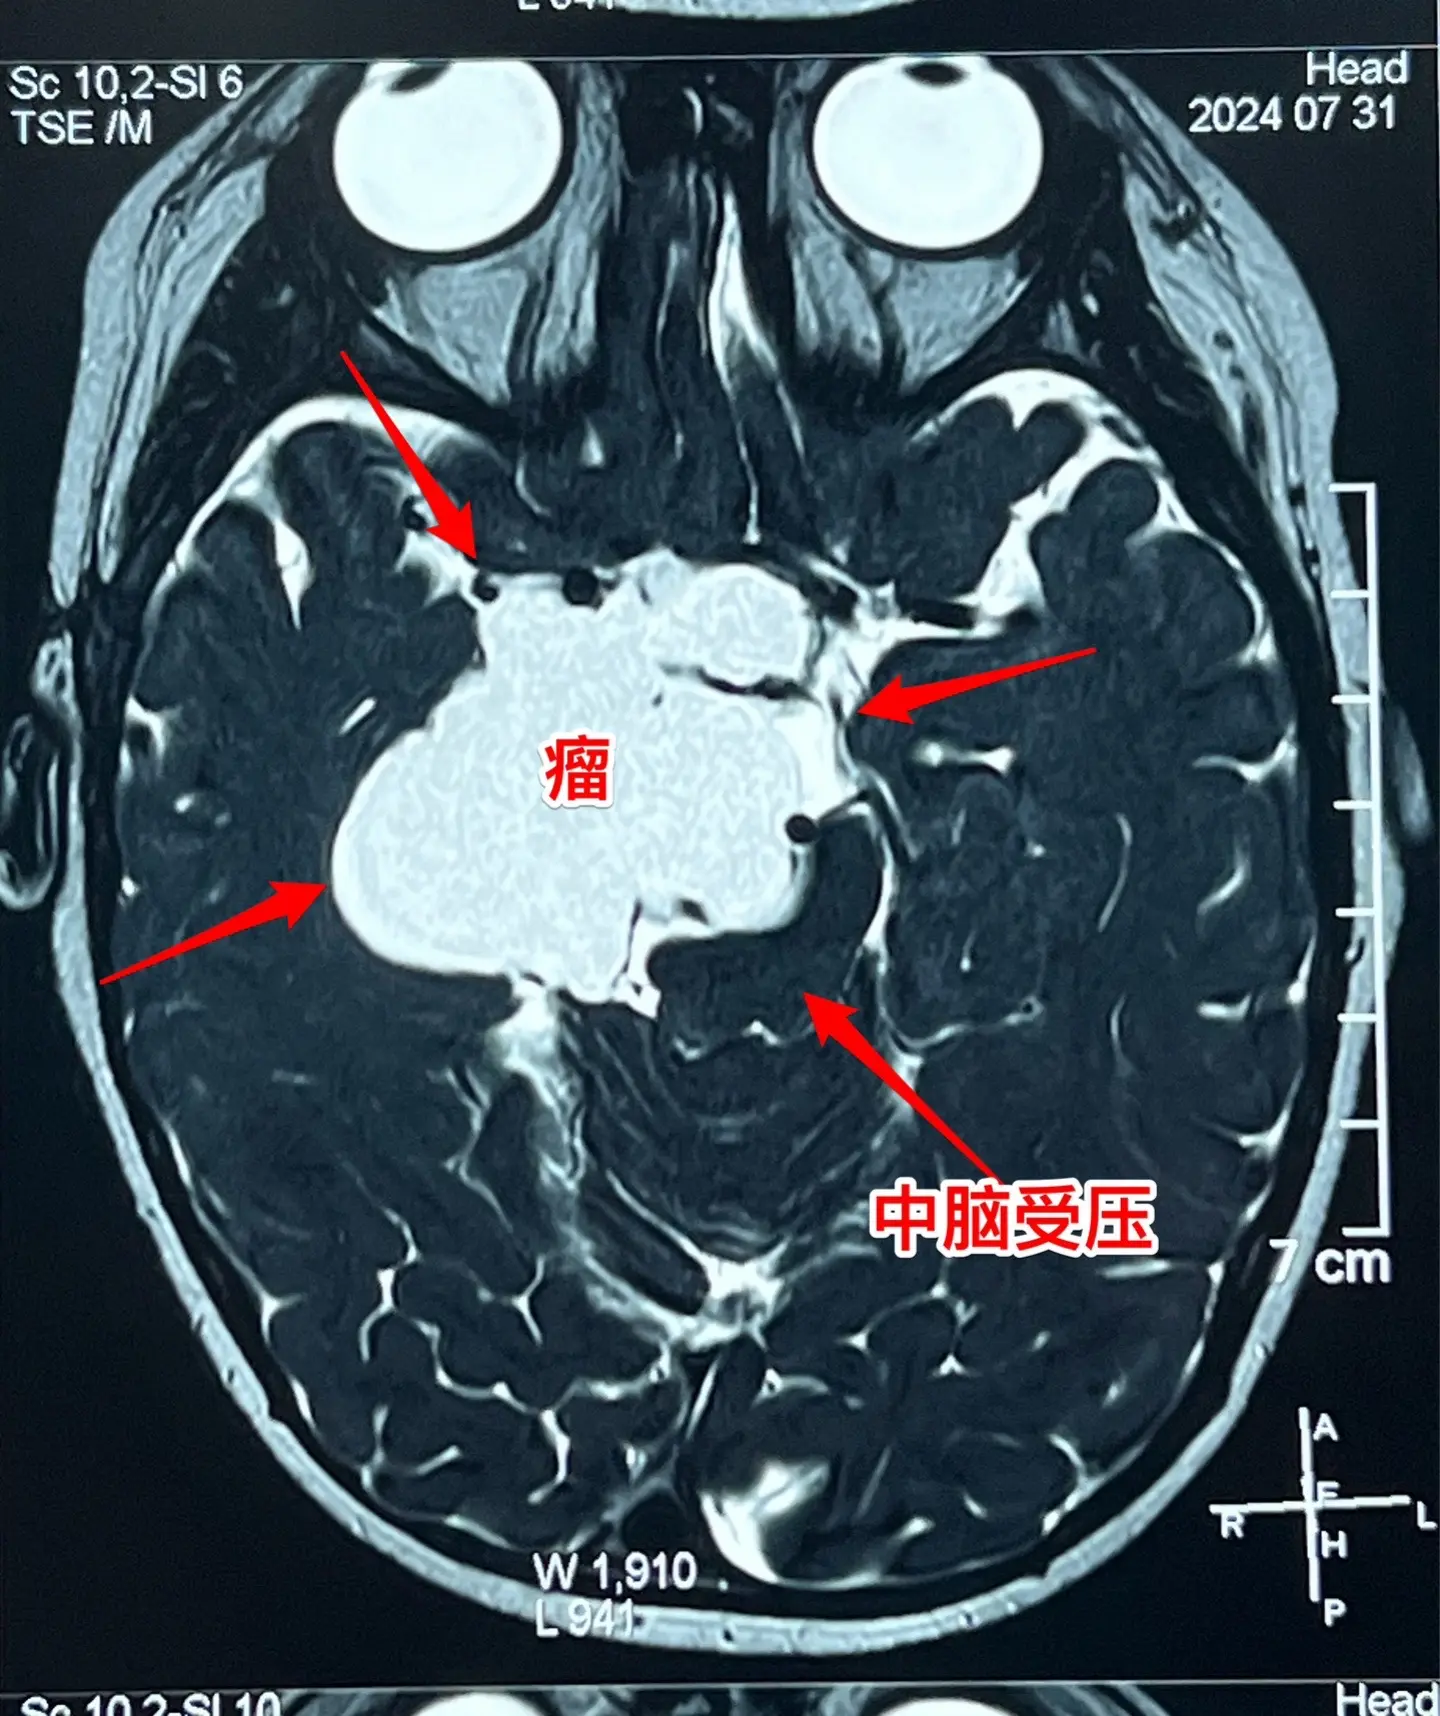

2岁孩子颅咽管瘤复发不得不接受手术。2岁多的山东女孩子,在颅咽管瘤手术后4个月(在山东省作的)发现右侧眼睑下垂越来越严重。复查磁共振显示颅咽管瘤复发了,肿瘤体积很大,患儿的左侧上下肢活动力量也变差了。 八月八日小朋友接受了人生中的第二次开颅手术。手术过程很顺利,也很艰难。一部分肿瘤囊壁菲薄,与周围血管粘连紧密,花费很长时间才讲肿瘤完全切除。 手术后患儿很快就清醒了,能说话,四肢都能活动。希望她能顺利出院。